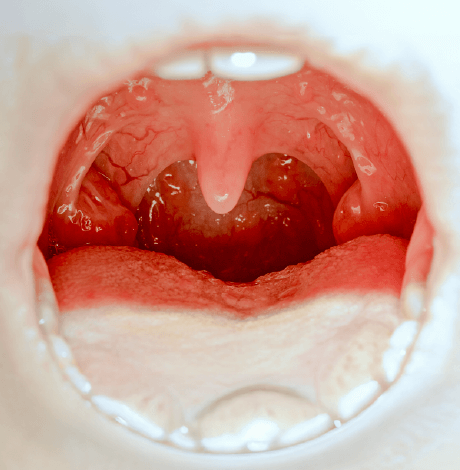

Eardrum surgery (tympanoplasty) is primarily performed on children to repair a deeply perforated tympanic membrane (eardrum) and prevent water incursion, which may arise due to a mid-ear infection, the growth of a tissue mass within the eardrum (cholesteatoma), or a sudden and loud noise behind.

The eardrum is a thin layer of tissue that vibrates in response to different sound frequencies and repairs itself, particularly in young children. At Yashoda Hospitals, our skilled otolaryngologists utilize state-of-the-art facilities to deliver precise, effective eardrum surgery. Through carefully planned treatment options, we provide comprehensive care tailored to achieve the best possible outcomes for our patients.